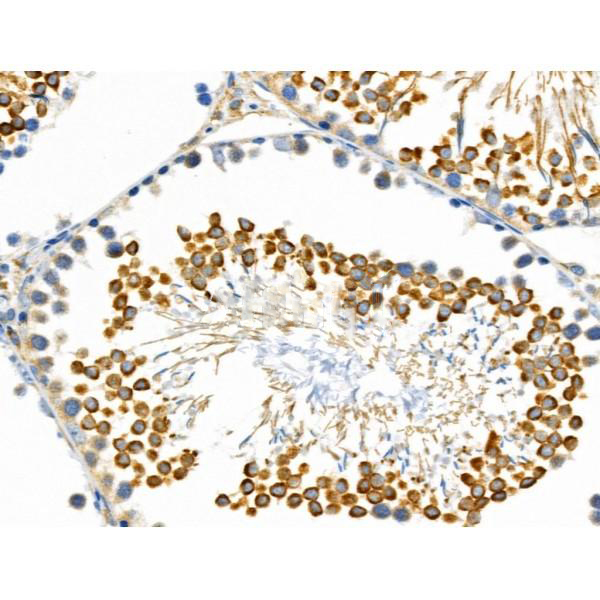

- 免疫组化&HE染色